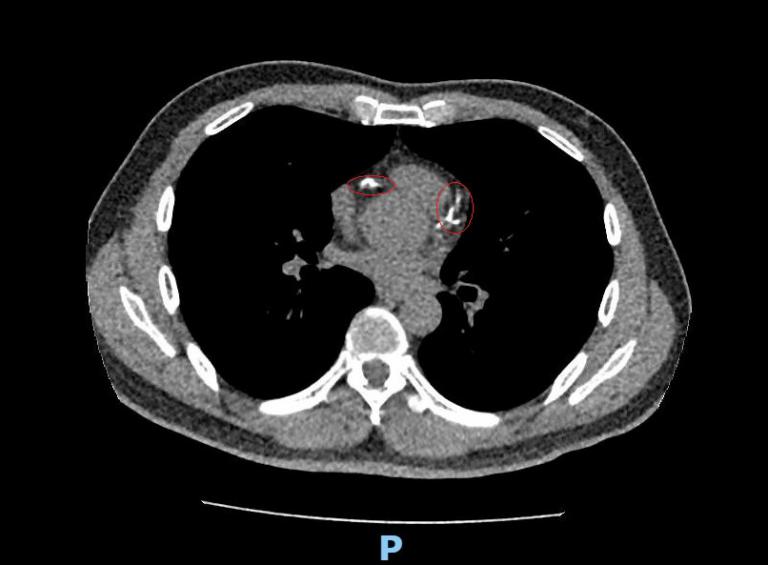

▲心臟冠狀動脈電腦斷層顯示林先生冠狀動脈鈣化阻塞。(圖╱彰化醫院提供)

▲李學林醫師指出,林先生進一步做心臟冠狀動脈電腦斷層,確認為3條主要冠狀動脈血管內鈣化狹窄達85%以上,若未及時處理,隨時可能引發急性心肌梗塞。(圖╱彰化醫院提供)

李學林表示,林先生日前接受肺癌篩檢時意外發現心血管鈣化,但無法確認是血管內或血管外鈣化。因患者平時已出現胸悶症狀,進一步做心臟冠狀動脈電腦斷層,確認為3條主要冠狀動脈血管內鈣化狹窄達85%以上,若未及時處理,隨時可能引發急性心肌梗塞。